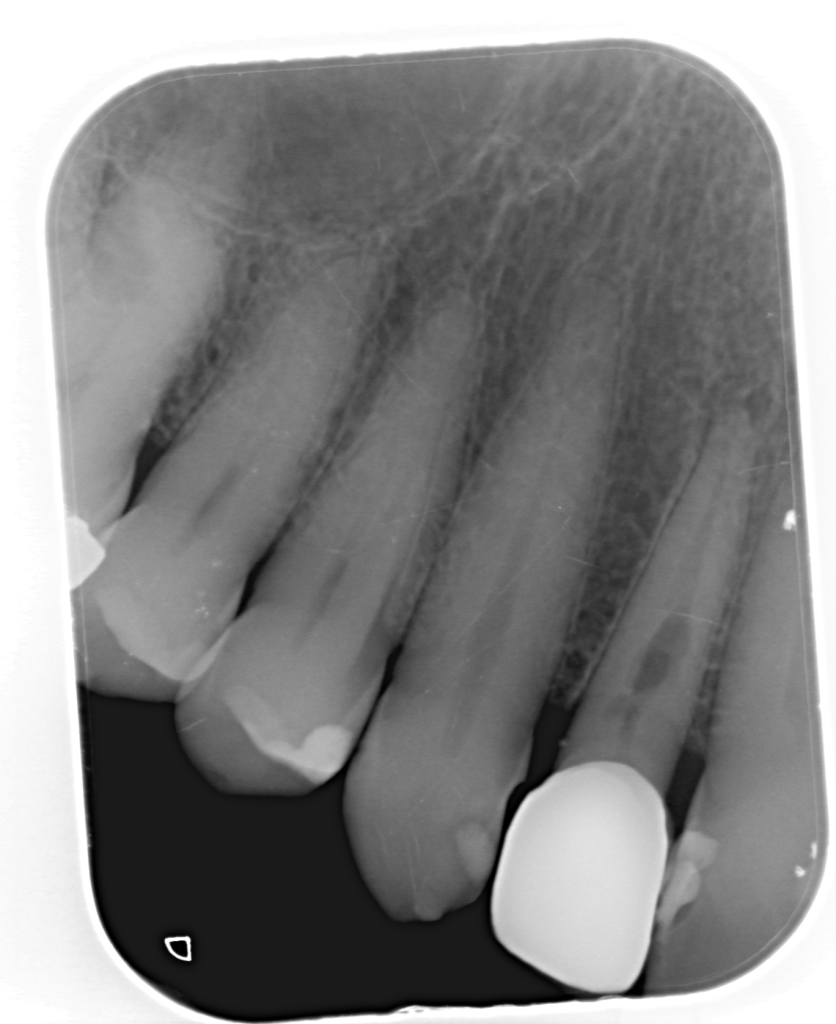

Reco preendo, 2o Molar superior